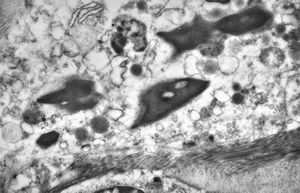

M, 3y. | cutaneous nerve